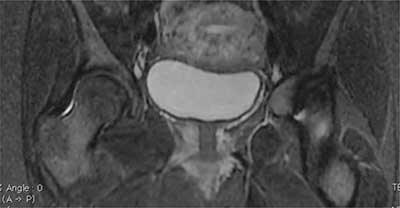

Figure 12

Inflammatory arthritis of sacroiliac joints in the postpartum: axial STIR a) and b) and frontal STIR c) MRI images show high signal intensity of the right and left joint space (*), subchondral bone (–>), and soft tissue (>) with no fluid collection.